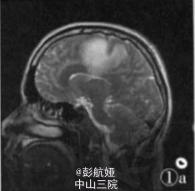

患者,男,34岁。以呼吸困难咳嗽咳痰伴上腹痛1周为主诉于2006年9月25日入院。发病时深呼吸咳嗽后胸口隐痛,痰中带血。血生化检查示:C反应蛋白22.4 mg/L(正常值0—8 mg/L)。心肌酶谱:谷草转氨酶46 U/L,乳酸脱氢酶2085 U/L,磷酸肌酸激酶57 U/L,肌酸激酶同工酶52 U/L,羟定酸脱氢酶192 U/L。凝血检查示:凝血酶原国际标准化比值1.01,凝血酶原正常对照12.90,凝血酶原时间13.0。外院完善寄生虫病原学检查示:痰虫卵(一),血清囊虫抗体弱(+),肺吸虫抗体(一),血吸虫抗体(一)。肿瘤四项检查示:AFP:328.1μg/L,CAl25:1.8μg/L,CAl99(一)。影像学检查示:B超“双乳头下3 cm×3 cm实性肿块,双腋下淋巴结肿大,颈部、手臂内侧、颅侧额叶左侧枕叶多发占位,肺部多发类圆形占位,肝脏脾脏多发占位,考虑为肝癌,颅内及肺内转移,不排除寄生虫病可能”,2006年10月1日行手臂肿块活检。

眼观:手臂肿块切除标本1个,大小4 cm×4cm×3 cm,其内见暗红色肿物,切面肿物界清,中央见大片暗红色出血、坏死区,周边少许灰红色区,质软。镜检:肿瘤组织内见大片出血、坏死,间质稀少;瘤细胞呈多边形,境界清楚,细胞质淡染或透亮,核圆形位于中央,核仁明显,此类细 胞成片排列,其间夹杂一团团的合体型细胞,胞质丰富、深染、嗜酸,细胞核多个、增大深染或皱缩(图2)。提示异型肿瘤细胞,巢团状浸润性生长,间质大片出血坏死,初步诊断为生殖源性恶性肿瘤,复查血HCG大于200 000 mlU/ml,尿HCG强(+),免疫组化结果显示:CK(+),HCG(+),HPL (+),AFP(一)。经病理提示绒癌可能后,再次体检发现患者一侧睾丸肿大,有男性乳腺发育特征。

病理诊断:男性绒毛膜癌,并发肝、肺、脑、手臂转移。本例并发肝、肺、脑、手臂多处转移灶,已经出现胸、腹部症状,经化疗无效,最后出现呼吸衰竭自动出院。